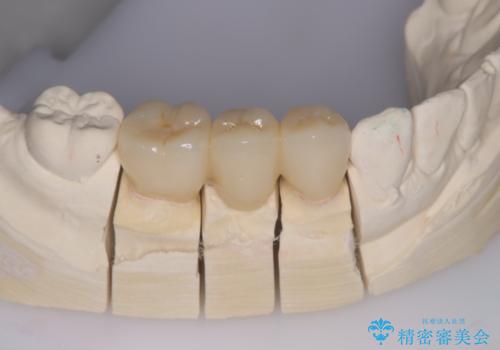

被せ物がとれた オールセラミックによるブリッジ治療

コアごと脱離して来院し、フェルールの獲得が厳しいためコアが立てられないので抜歯することになりました。

インプラントとブリッジの治療を提案し早く噛めるようにしてほしいという要望があったためブリッジにて治療をすることになりました。